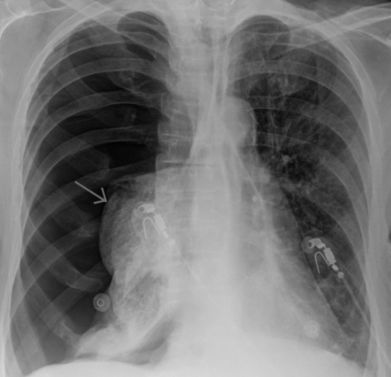

• рентгенография органов грудной клетки;

• КТ;

• УЗИ;

• функциональное исследование внешнего дыхания;

• торакоскопия;

• плевральная пункция;

• лабораторные исследования биологических материалов (кровь, моча, плевральная жидкость).

• рентгенографии грудной клетки;

• компьютерной томографии;